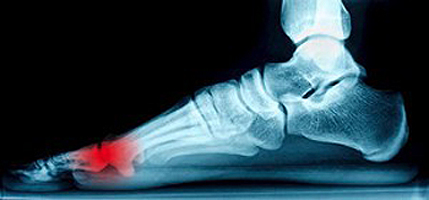

The Location of the Sesamoid Bones

The bones that are found surrounding the joints in the foot are referred to as sesamoid bones. Research has confirmed the big toe contains different types of these particular bones and they have specific functions, which includes providing stability while walking. If an injury should occur to one or more of these bones, inflammation is likely to develop and this typically results in severe pain and discomfort. This is referred to as sesamoiditis, and generally occurs from repetitive activity that may be associated with dancing, basketball, or tennis. Patients who experience this condition often notice gradual pain developing in the foot, in addition to swelling and tenderness surrounding the affected joint. The first phase of treatment will often include rest and cessation from the activity that has caused this ailment. It’s suggested to speak to a podiatrist if you are afflicted with sesamoiditis for further treatment options that are correct for you.